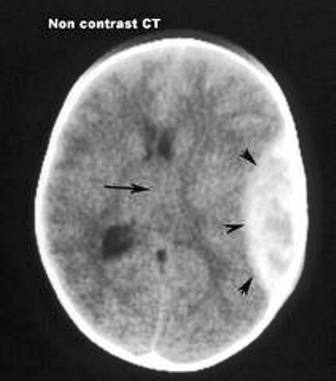

Hình ảnh CT cho thấy khoảng máu tụ rất lớn ngoài màng cứng trên đầu trẻ

Sáng cùng ngày, cháu Đ. được mẹ chở đi học bằng xe gắn máy nhưng không đội mũ bảo hiểm. Gặp quãng đường trơn trượt, người mẹ bị ngã xe, cả hai mẹ con té văng ra đường, cháu bé dập nát vành tai trái và rách da đầu. Sau khi được bệnh viện địa phương sơ cứu, cháu được chuyển đến Bệnh viện Nhi Đồng 2, kết quả chẩn đoán hình ảnh cho thấy cháu đã bị chấn thương nặng ở vùng đầu.